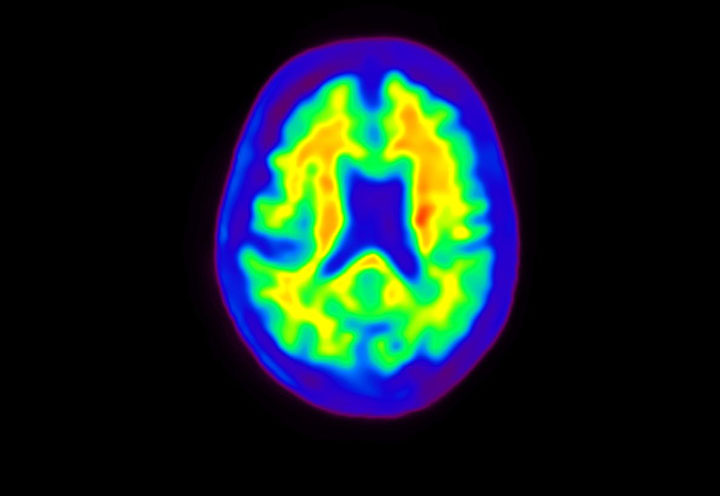

Head / Case4 : Amyloid

Courtesy : Kindai University Hospital

- Imaging protocol

- Injected dose: 3.21 MBq/kg, 18F-Flutemetamol

- Uptake time: 100 minutes

- Scan time: 20 minutes